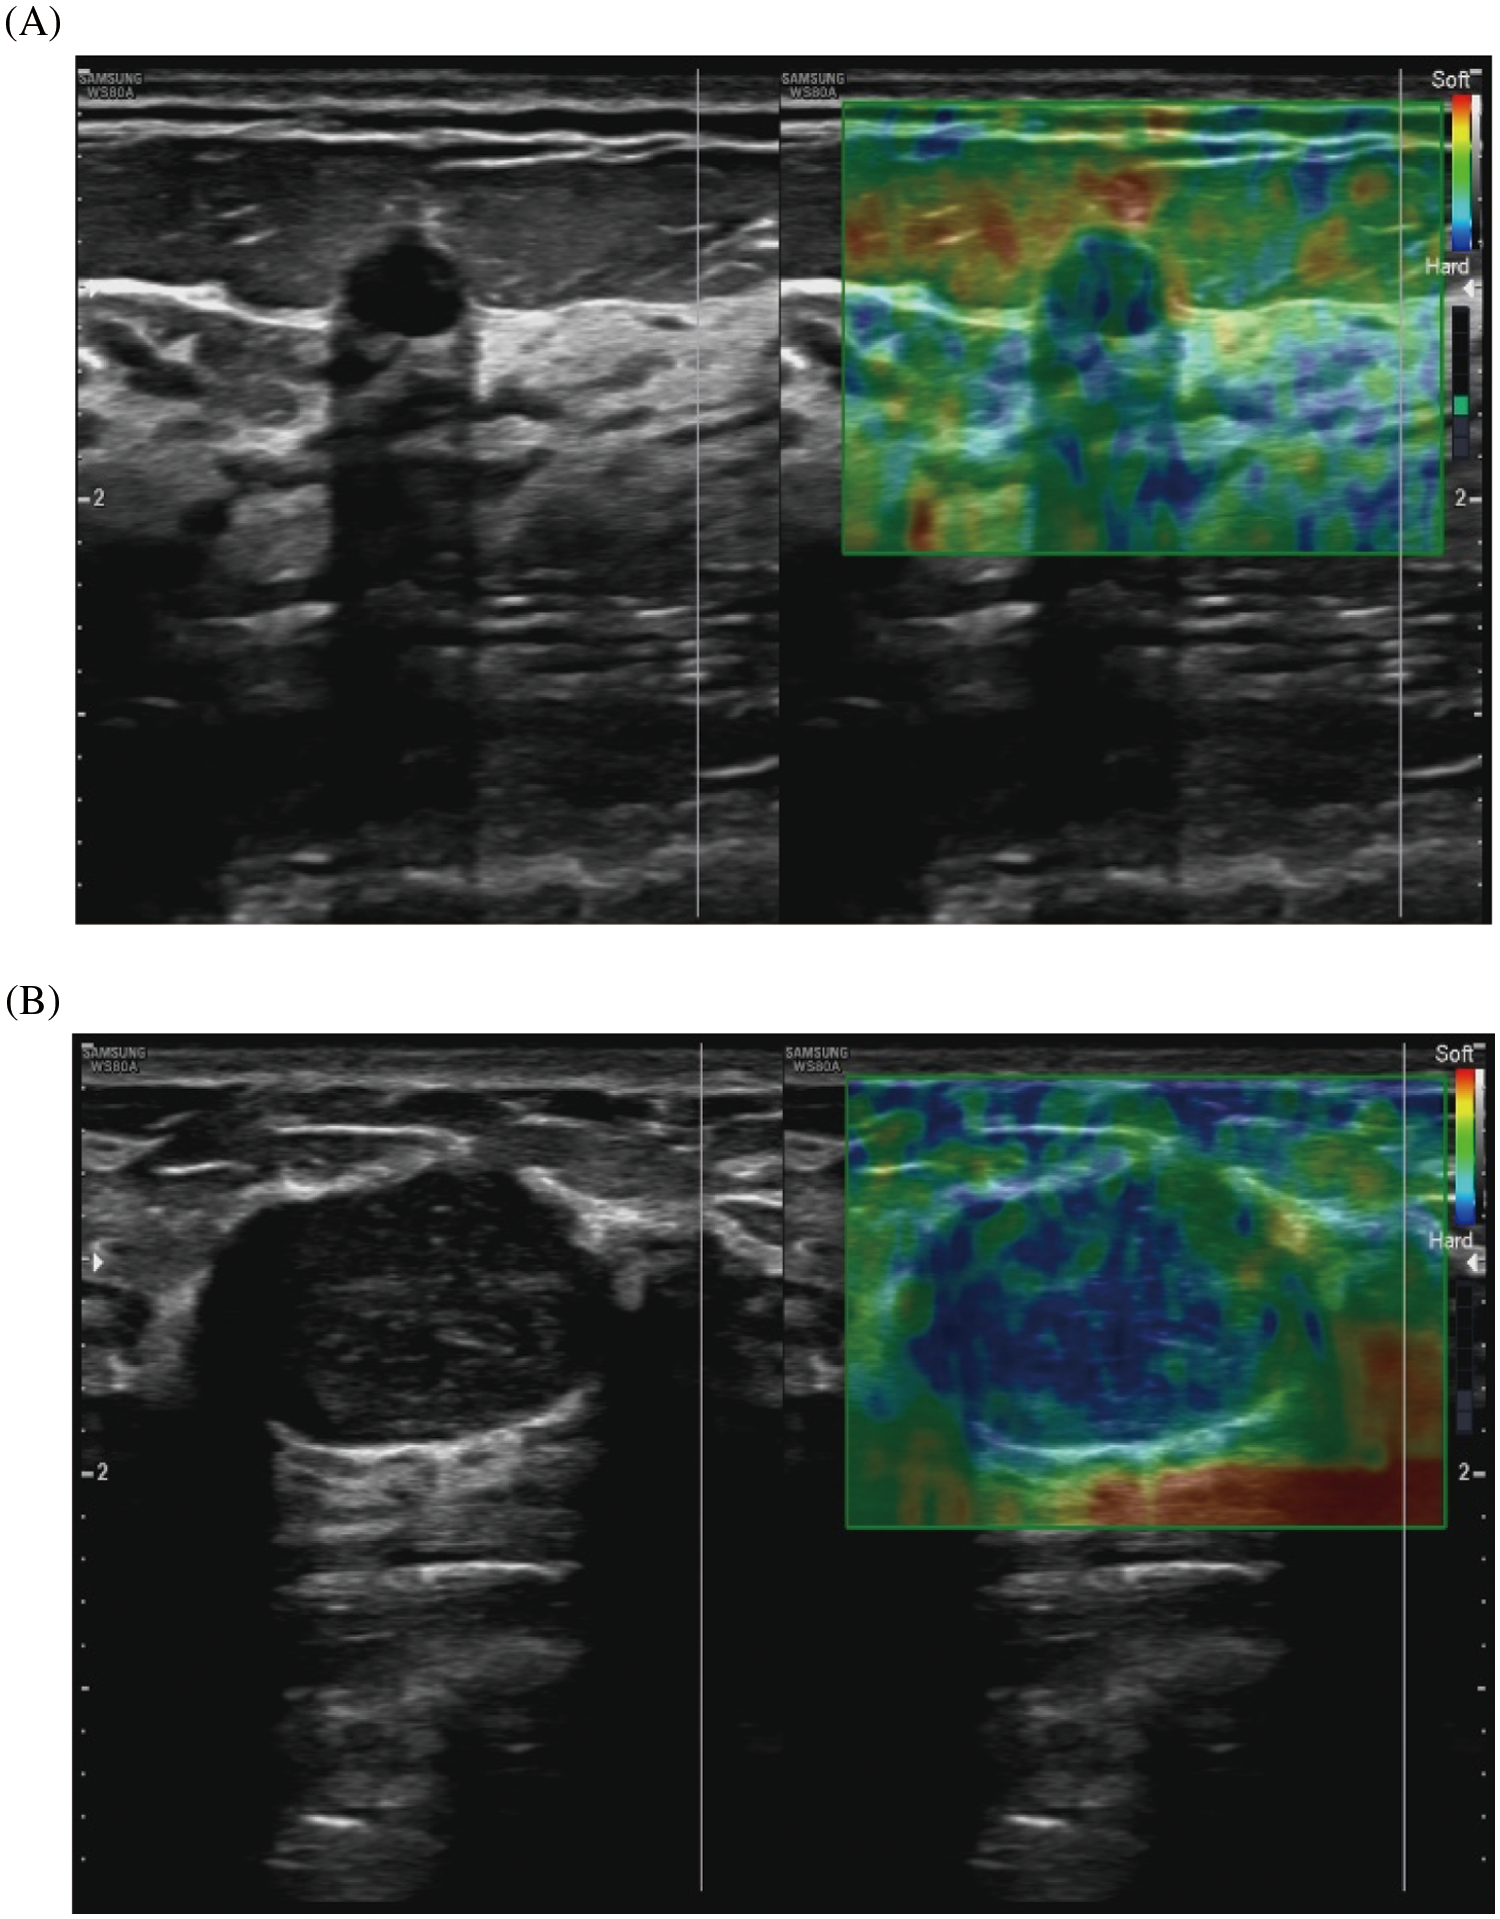

Our study showed that the average value of the ultrasonic elastography score (UES) of benign breast lesions was 2.91 ± 0.69, and the average value of the UES of malignant breast lesions was 3.80 ± 0.58. The difference between the two groups was statistically significant (Table 2). Representative images of ultrasonic elastography of benign and malignant breast lesions are shown in Fig. 2. To further explore the value of UES in the diagnosis of BC, ROC curve analysis was employed and showed that the AUC was 0.809 (95% CI: 0.714–0.904) (p < 0.001), with a sensitivity of 0.717 and specificity of 0.806 (Fig. 3), indicating that UES has significant clinical significance in the differentiation of benign and malignant breast lesions.

Figure 2: Representative images of ultrasonic elastography of benign and malignant breast lesions. (A) This breast lesion scores 2 points with the 5-point method: (left) the image of conventional ultrasound, (right) the image of ultrasonic elastography. (B) This breast lesion scores 4 points with the 5-point method: (left) the image of conventional ultrasound, (right) the image of ultrasonic elastography